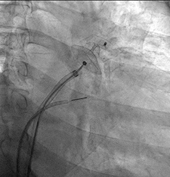

Figure

1. LAAO implantation under ICE guidance, which can be safely performed under

local anesthesia

● Real-Time Guidance: Using the dual, real-time

guidance of ICE or TEE and X-ray fluoroscopy, the catheter is precisely

delivered and safely advanced across the interatrial septum into the left

atrium.

● Implantation and

Confirmation: The selected Occluder is released,

expanding securely into the LAA opening. The physician performs multi-angle

checks to ensure the position is stable and there is no residual leak.